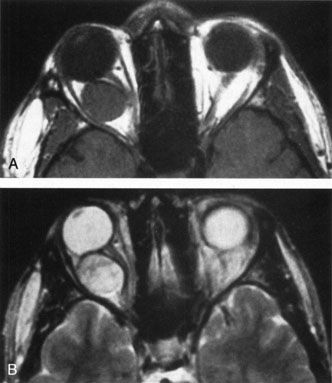

Investigations

Contrast-enhanced CT of the orbits with direct and coronal cuts is the radiologic study of choice for these patients.45 A well-demarcated, encapsulated oval or rounded mass is revealed, which is typically intraconal in the lateral part of the middle third of the orbit (Fig. 5) but occasionally may extend to the extraconal space.42 Septa within the tumor may be apparent on high-resolution CT. The posterior pole of the globe frequently is indented by the rounded anterior margin of the tumor.42 The optic nerve typically is displaced rather than surrounded by the tumor. Subtle outward bowing of the lateral orbital wall or increase in orbital size may be present, consistent with a long-standing, slowly growing mass lesion.10,42 Enhancement with intravenous contrast occurs and may be homogeneous or inhomogeneous.10,45 Rarely, cavernous hemangiomas may occur as an intraosseous tumor within the orbital or facial bones.42,53–55 Although usually an isolated intraorbital lesion, multiple lesions in one orbit occurred in 8 of 164 (5%) patients of three combined large studies,10,42,45 and bilateral multiple cavernous hemangiomas also have been described.56 In contrast to patients with venous flow malformations in which phleboliths are common, phleboliths are rare in cavernous hemangiomas. Three large studies comprising 164 patients with cavernous hemangioma all reported that no calcification was detected within the tumor.10,42,45If the diagnosis is still unclear or if better definition of details and localization of the lesion is required, then MRI should be performed. Magnetic resonance imaging demonstrates nonspecific characteristics of a lesion isointense to muscle and gray matter on T1-weighted images and hyperintense on T2-weighted images (Fig. 6).57 The lesions show initial central patchy enhancement, which fills up homogeneously within 20 to 60 minutes.58 If ultrasonography is performed, B-scan ultrasonography shows a well-circumscribed mass with a sharply defined anterior acoustic border.23 A-scan ultrasonography shows high reflectivity of the echo signals resulting from the multiple blood-filled vascular channels, regular internal structure with a higher anterior and posterior spike marking the capsule, and moderate sound attenuation (angle of decrease of the echo spike within the lesion).24 Arteriography is not indicated.

Fig. 5. Cavernous hemangioma. Contrast-enhanced axial computed tomography scan shows a well-demarcated, oval intraconal mass in the lateral part of the middle third of the orbit. Note the enhancement within the lesion, which in this instance is inhomogeneous, but can also be homogeneous.

Fig. 6. Cavernous hemangioma. Axial magnetic resonance imaging demonstrates a well-defined, homogeneous intraconal mass that is isointense to muscle and gray matter on T1-weighted image (A), and hyperintense on T2-weighted image (B). Note the displacement of the optic nerve and indented posterior globe.